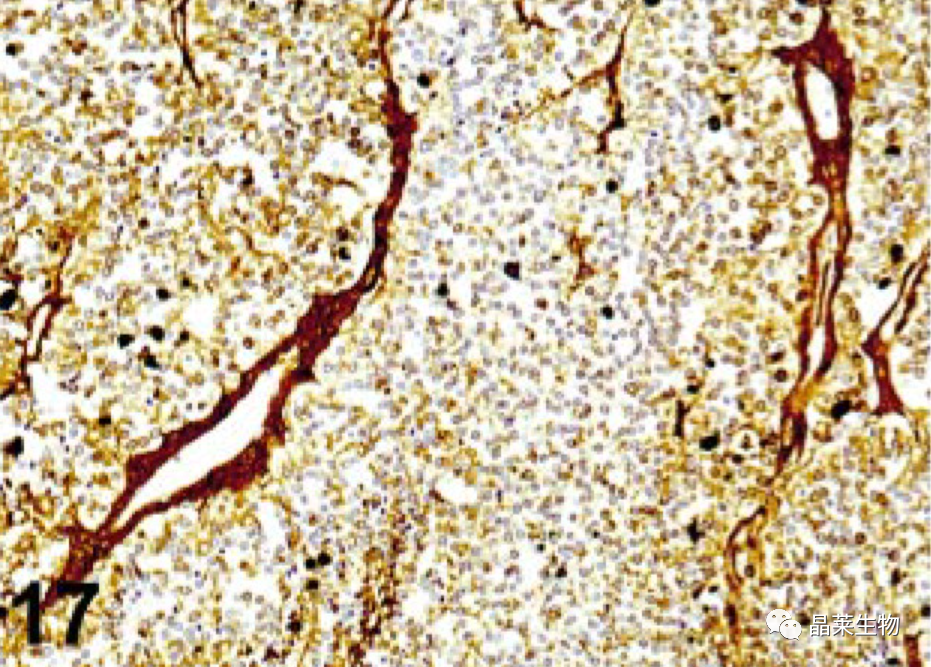

天然存在于红细胞(假过氧化物酶)、粒细胞(髓过氧化物酶)和神经元中的酶活性可与DAB反应,产生与特异性免疫染色无法区分的棕色产物。尽管在福尔马林固定过程中内源性过氧化物酶活性几乎完全被破坏,但用稀释的(0.003-3%)H₂O₂对组织切片进行预处理在甲醇中将进一步降低或完全消除红细胞的假过氧化物酶活性和髓系细胞中的过氧化物酶活性。

在大量出血或酸性血红素的组织切片中,更强(10%)H₂O₂的溶液可能需要去除这种内源性活动,或在浓度较低的溶液中孵育更长时间。H₂O₂用途–不建议将甲醇用于检测细胞表面Ags的标本;此外,使用甲醇可能会将冷冻切片从载玻片上分离出来。在这些情况下,内源性过氧化物酶活性可以被(0.3%)H₂O₂的混合物抑制在0.1%叠氮H钠溶液中或H₂O₂用蒸馏水稀释。使用非常灵敏的检测系统时,内源性过氧化物酶背景可能更明显。为了减少这种背景,H₂O₂需要增加浓度或使用替代酶。其他对Ag检测有不同影响的方法也抑制内源性过氧化物酶活性。